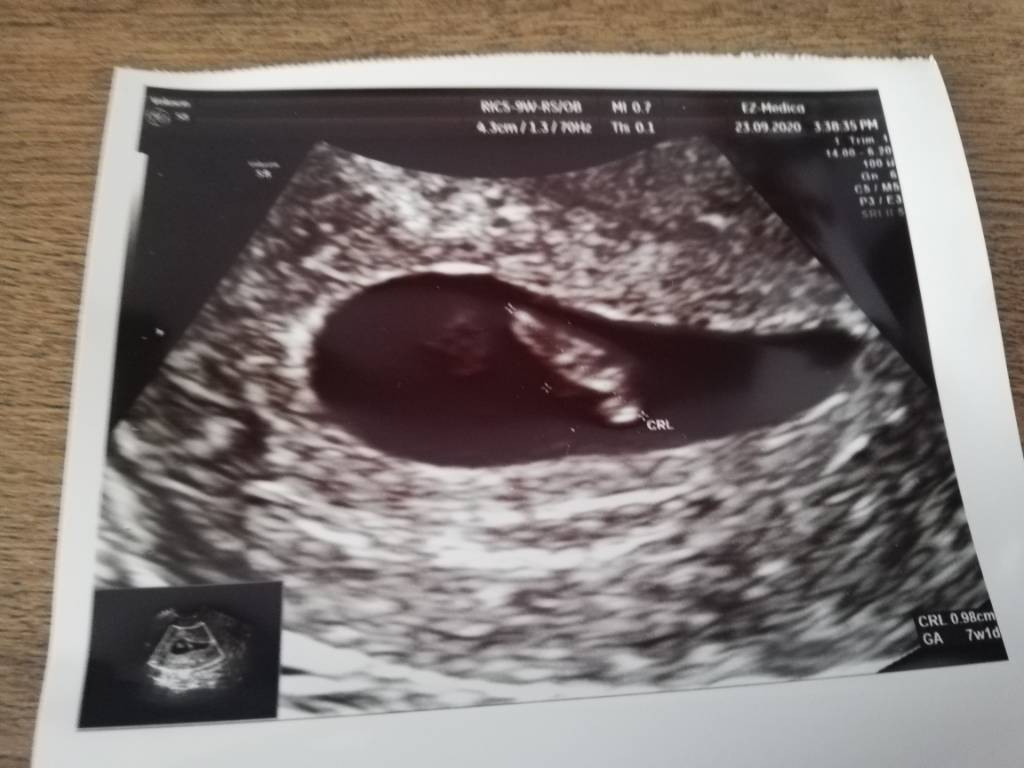

No to ja wam pokaże coś bo okres miał byc dzisiaj ale już wczoraj coś czułam że coś nie tak bo zawsze mega dołem mnie bolał brzuch dzien przed okresem

zdjecie z dzisiaj rano pol godziny temu robione